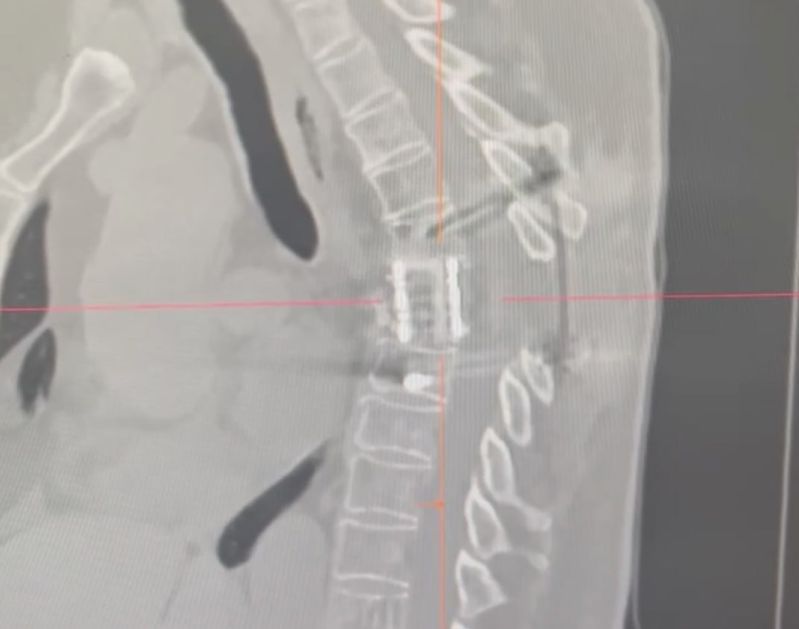

В пресс-службе БСМП рассказали о спасении 69-летней женщины, которая обратилась в больницу с жалобами на отсутствие движений в ногах и боли в области грудного отдела позвоночника.

После обследования женщины нейрохирурги БСМП выяснили, что у пенсионерки идет разрушение тел грудных позвонков. Было принято решение об экстренном оперативном вмешательстве для сохранения функций спинного мозга.

«В ходе первого этапа пациентке установили импланты для стабилизации позвонков. После операции проводилась медицинская реабилитация для восстановления состояния женщины. Через несколько месяцев после вмешательства у нее появилась чувствительность в ногах и восстановился минимальный объем движений. Второй этап операции был выполнен в Бурятии впервые. В её ходе было произведено удаление отломков и замена тел 6-го и 7-го грудных позвонков на титановые импланты. Такое вмешательство потребовало от врачей-нейрохирургов высокого мастерства, так как операция проходила в грудной полости - рядом располагались легкое, сердце и крупные сосуды», - рассказали в БСМП.

Фото: БСМП